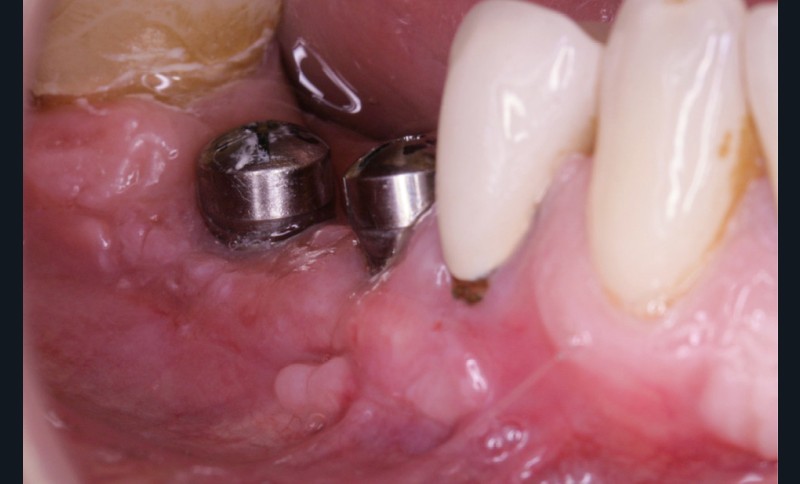

La greffe épithélio-conjonctive (GEC) [7, 8] consiste au remplacement du tissu parodontal existant par un greffon épithélio-conjonctif dont l’indication principale est l’augmentation en hauteur et en épaisseur du tissu kératinisé (fig. 2). Elle peut aussi être utilisée dans le recouvrement radiculaire (avec des résultats en termes de recouvrement inférieurs à ceux des techniques de greffe de conjonctif enfouie), l’aménagement des crêtes édentées, l’aménagement péri-implantaires [9, 10] (fig. 3), ou en association avec un traitement ortho-parodontal [11]. Le principal défaut de cette technique est son aspect inesthétique ; elle sera donc réservée à des zones non visibles comme les incisives mandibulaires ou les zones postérieures.

De nombreuses techniques de lambeaux déplacés latéralement, lambeaux déplacés coronairement (fig. 4), enveloppes ou tunnels (fig. 5) ont fait l’objet de publications et présentent des résultats quasi identiques en termes de recouvrement. Leurs points communs sont un recouvrement complet du greffon, une dissection en épaisseur partielle suffisante pour assurer un positionnement du lambeau sans tension et l’absence (quand cela est possible) d’incision de décharge. Le choix d’une ou l’autre technique dépend surtout de l’expérience du praticien et de la quantité de tissu disponible apicalement ou latéralement.